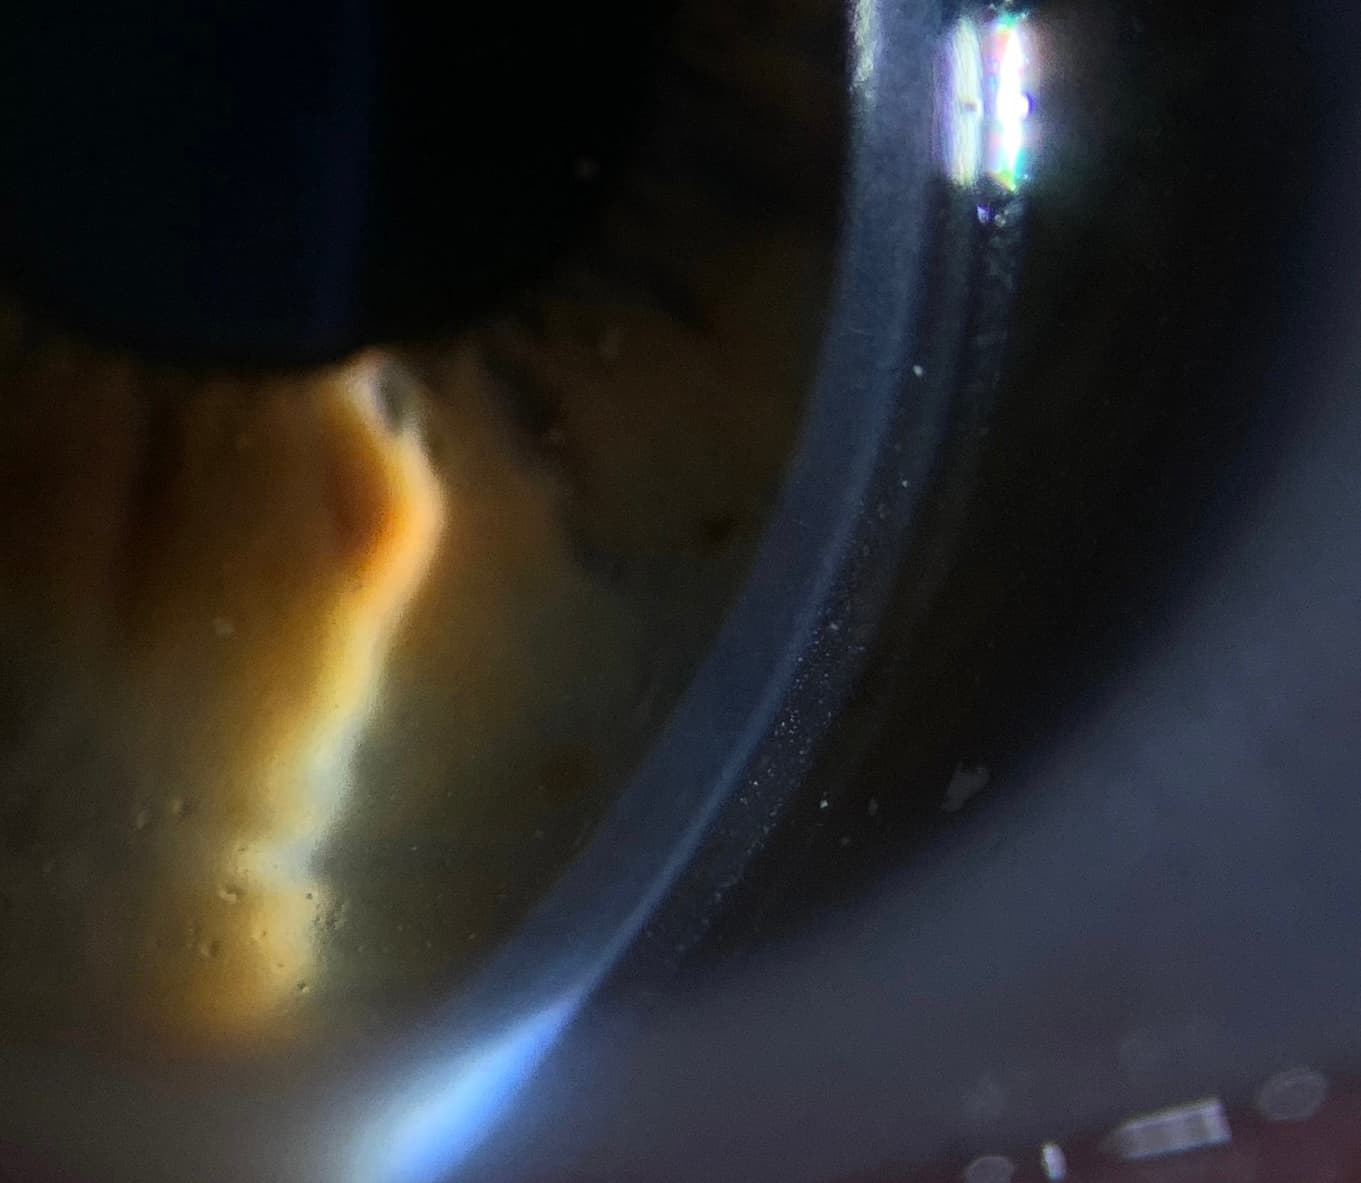

Scleral Lenses for Dry Eye Relief YouTube